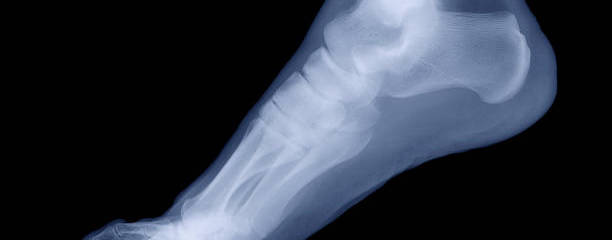

Radiografía (RX)

La radiografía permite visualizar los huesos y articulaciones del pie y del tobillo, detectar deformidades, fracturas, artritis o alteraciones en la alineación.

Es una herramienta clave para valorar la estructura ósea y planificar tratamientos ortopodológicos o quirúrgicos de manera precisa.